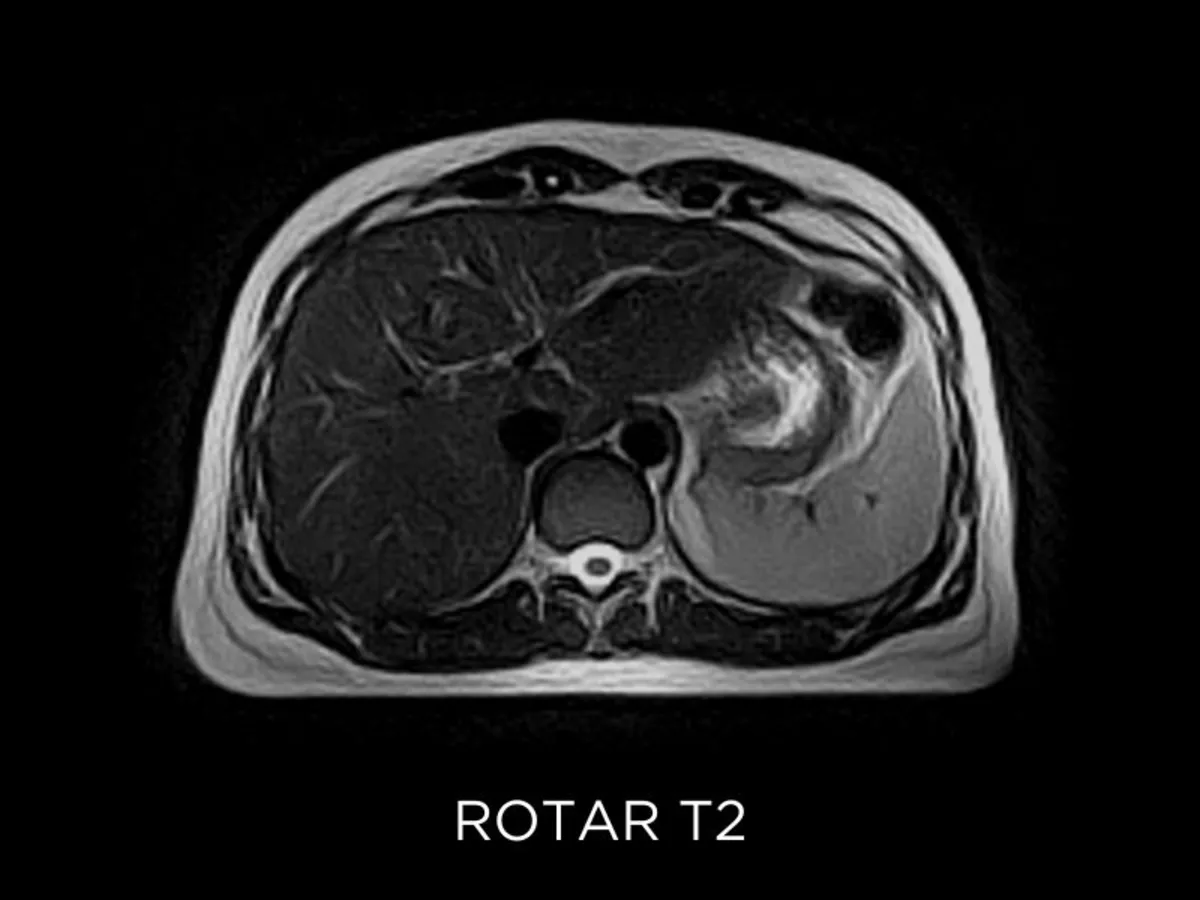

• ROTAR: in FSE sequences, it reduces moving artifacts on free-breathing acquisitions.

Abdominal imaging clinical images